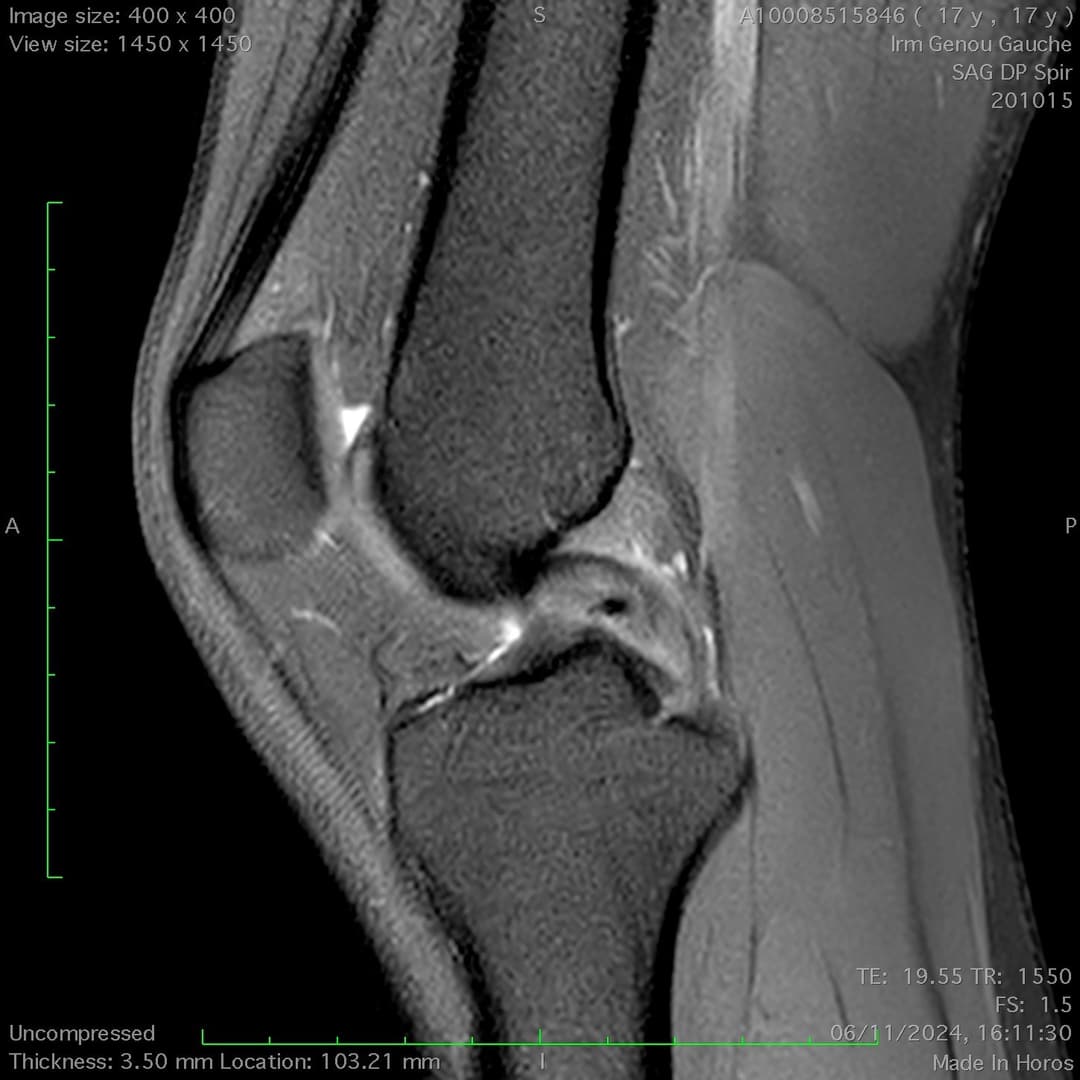

Lésion traumatique partielle du ligament croisé postérieure avec atteinte traumatique inférieure à 50% des fibres ligamentaires, notamment du corps et de l'enthèse rétro-tibiale.